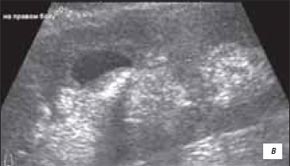

а) При полипозиционном УЗИ - гигантский дивертикул верхней чашечки правой почки с феноменом "кальциевого молока", создающим меняющийся горизонтальный уровень между эхонегативным и эхопозитивным содержимым полости дивертикула.

б) Серия полипозиционных КТ-грамм в положении пациента на спине, животе и правом боку - горизонтальный меняющийся уровень в полости дивертикула при феномене "кальциевого молока" в нем.